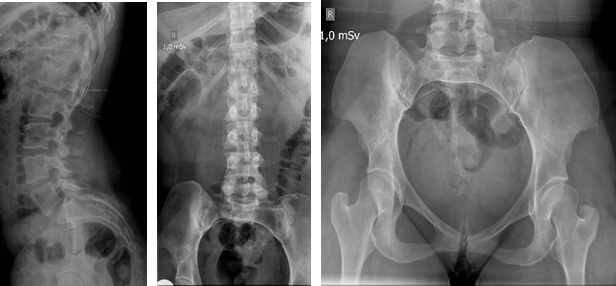

Síndrome de Grebe. Reporte de un caso. [Grebe syndrome. Case report.]